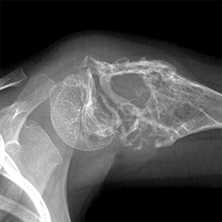

(Слева) КТ, аксиальная проекция, костный режим: случайно выявленный в крестце костный островок. Однородный склеротический очаг имеет типичные признаки угасания на периферии с переходом в сопряженную кость. Это может давать характерный несколько инфильтративный вид щетки или звездчатость.

(Справа) Сцинтиграфия, задняя проекция: у этого же пациента визуализируется фокальный округлый очаг накопления, соответствующий костному островку. При достаточно большом размере патологического очага, его склеротическая природа обусловливает позитивную сцинтиграфию. (Слева) КТ сканография: довольно крупный костный островок. Он имеет однородную плотность и расположен в костномозговом пространстве. У мужчины средних лет, как в данном случае, такая картина могла быть расценена как метастаз при раке предстательной железы.

(Справа) КТ, аксиальная проекция, без контрастного усиления: патологический очаг сливается с нормальной окружающей костью и имеет спикулы на периферии, типичные для костного островка. Не удивляйтесь, обнаружив, что при сцинтиграфии данное образование имеет вид горячего очага. Достаточно крупный эностоз характеризуется повышенным накоплением. (Слева) Рентгенография в ПЗ проекции, выполненная по причине боли в противоположном тазобедренном суставе: случайно выявленные склеротические очаги в левой подвздошной кости. При сцинтиграфии (не представлена) патологического накопления не выявлено. Тем не менее, такое необычное скопление склеротических очагов позволяет предположить наличие метастазов.

(Справа) КТ, аксиальная проекция: у этого же пациента определяются патологические очаги с заваренными краями, плотность которых соответствует кортикальной кости. Эти очаги оставались стабильными через четыре года и, поэтому, не требовали дальнейшего наблюдения. Они представляют собой необычное скопление эностозов.